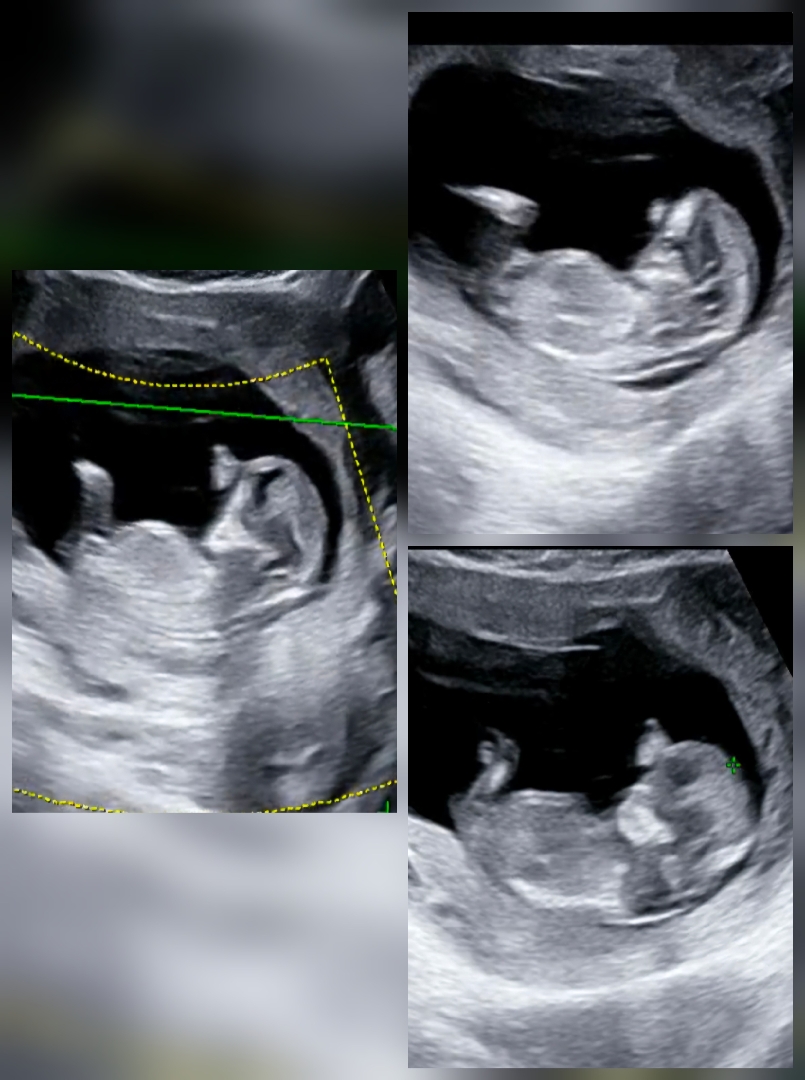

11주 6일 각도법 같이 봐주실 수 있을까요 😉

1차 기형아 검사 하면서 목투명대 정상 확인했는데, 아들 딸 상관없이 건강만 하면 되지만 그래도 성별이 궁금하긴 하네요 ㅎㅎ 초산이라 저는 봐도 잘 모르겠어서 각도법 고수이신 분들 봐주시면 감사하겠습니다 🙇🏻♀️

아들같긴해요 근데 반전있을수도요 ㅋㅋㅋ